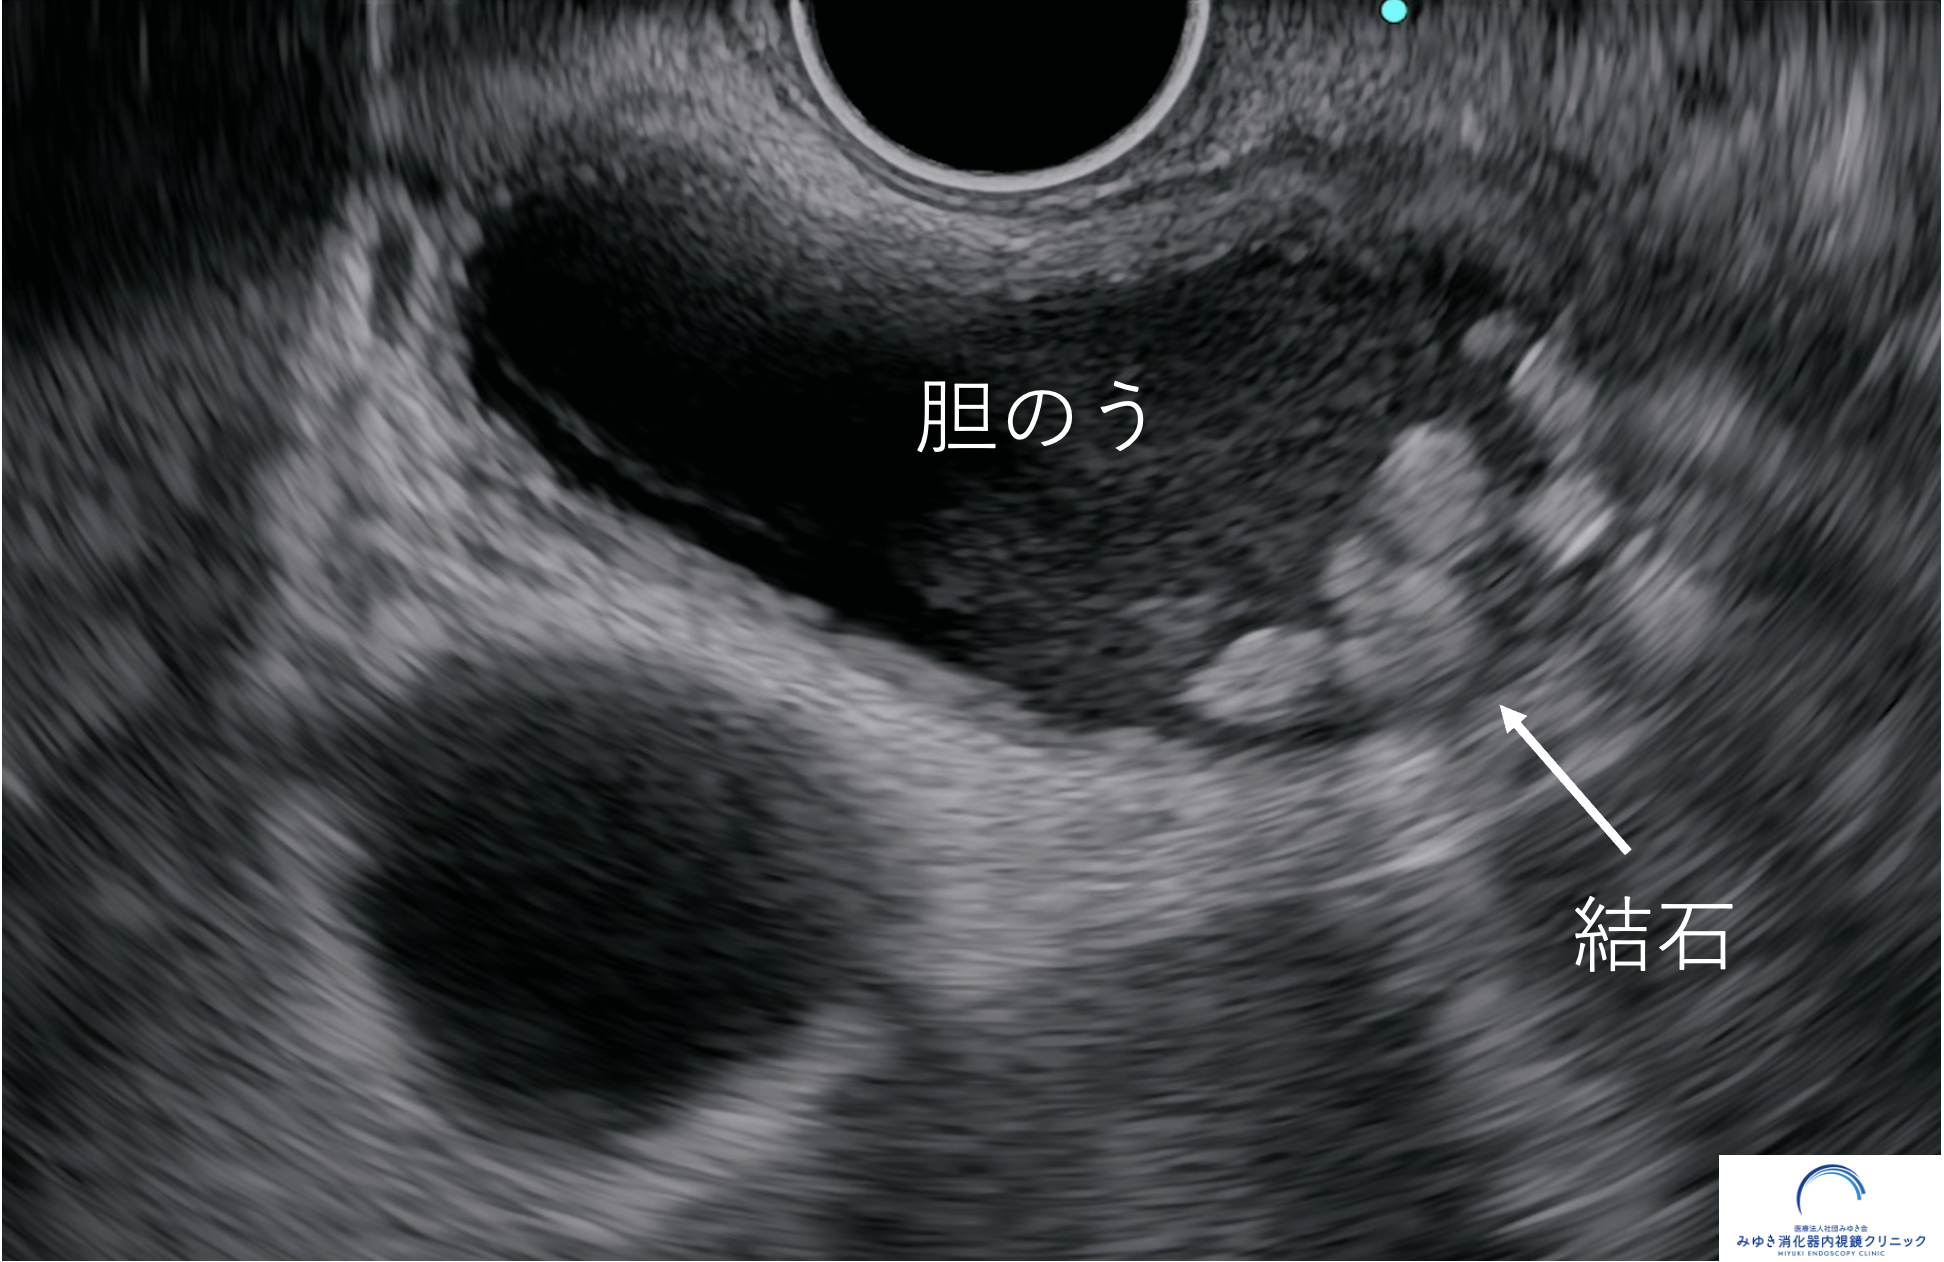

胆のう結石(超音波内視鏡検査)